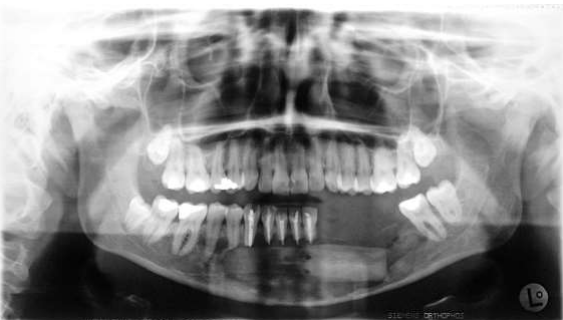

Fig 7: Oktober 2005: trial excision, suspected recurrence fibrosarcoma right lower jaw

Fig 8: 2001/12: recurrence fibrosarcoma, anterior resection floor of mouth, histology: fibromatosis with highly differentiated soft tissue sarcoma (G1)

Figure 7

Figure 8